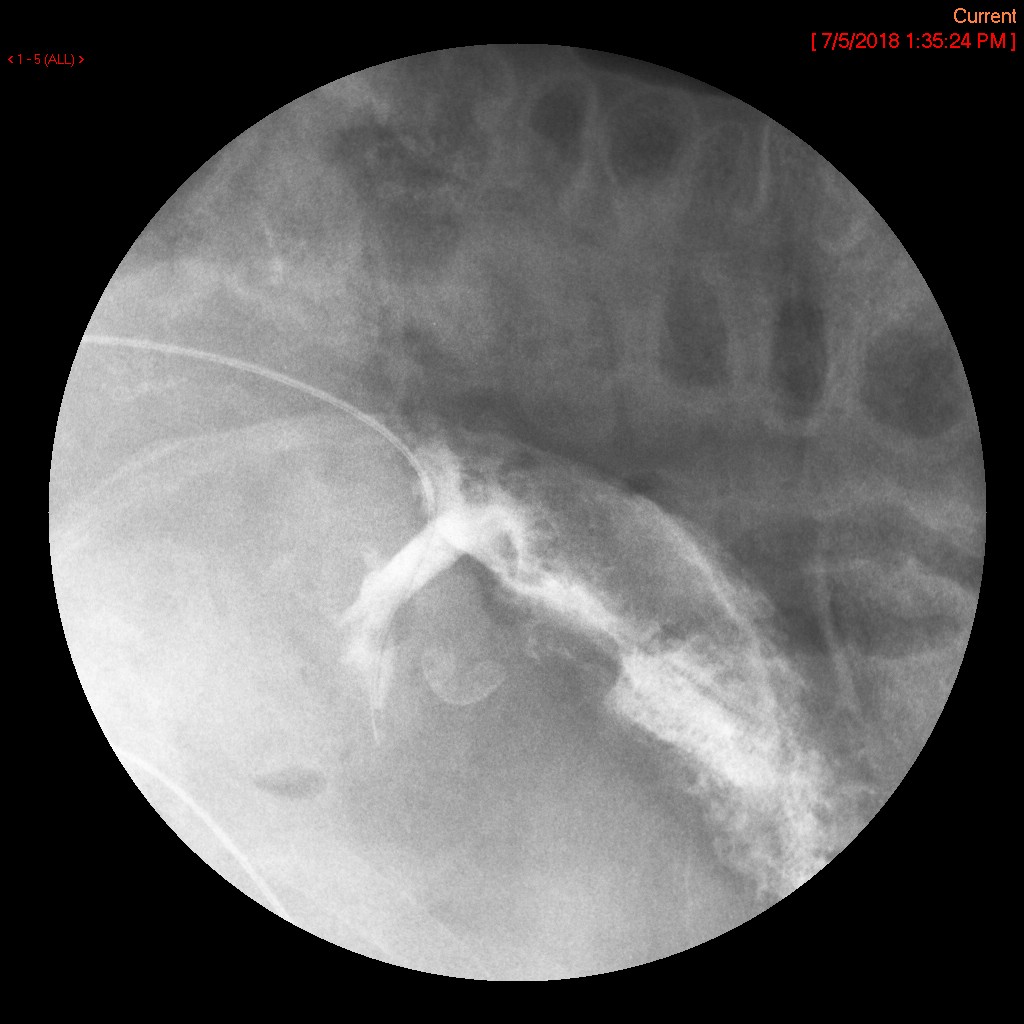

- Obtain a spot film of the contrast material filling the gastric pouch and proximal roux limb

(key image 2).

- Repeat steps b and c except have the patient positioned in the left posterior oblique position

(key image 3).